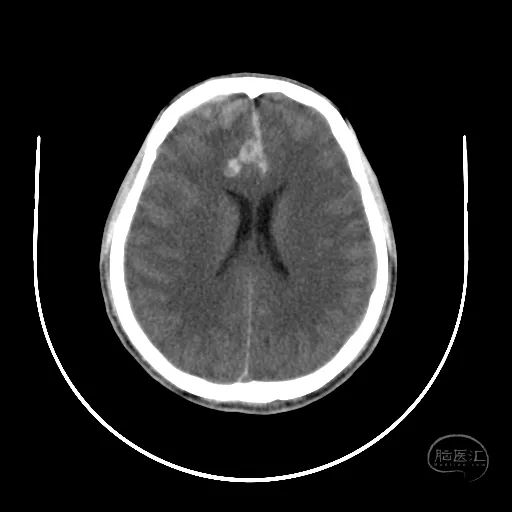

术后第一天复查CT显示后颅窝血肿清除,第四脑室隐约可见。

患者昏迷状,GCS评分3分,双侧瞳孔等大等圆,直径3mm,对光反射迟钝。

额叶血肿清除后,水肿明显。

额叶残余少量血肿,脑室引流管在位。

骨窗见枕骨大孔开放。术中清理枕骨大孔骨折时,无明显出血。

术后18天复查颅脑CT,显示小脑半球恢复良好,第四脑室清晰。

硬膜外血肿基本吸收。

额叶水肿减轻。

脑室稍扩张,骨窗张力较低。

患者GCS评分8分,已转入普通病房,继续康复治疗。